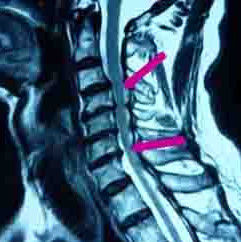

常規X線平片,主要是側位片上可清晰地顯示頸椎椎管矢狀徑。凡在標準投照距離180cm攝出的平片上矢狀徑小於12mm時,即具有診斷價值;12~14mm時有診斷參考意義;而在10mm以下時完全可以確診。此外亦可依據椎體與椎管的矢狀徑比值進行判斷,小於1∶0.75即屬異常,小於1∶0.6時具有診斷意義,比值在1∶0.5以下時完全可以確診。MRI檢查

可清晰地顯示椎管矢狀徑的大小、形態及其與脊髓受壓的關係。CT檢查主要顯示骨組織,而MRI檢查則對軟組織顯像較為清晰,因此二者結合起來最為理想,不僅有利於診斷,更有利於對椎管內組織狀態的判定,以決定治療方案及術式的選擇。除外診斷